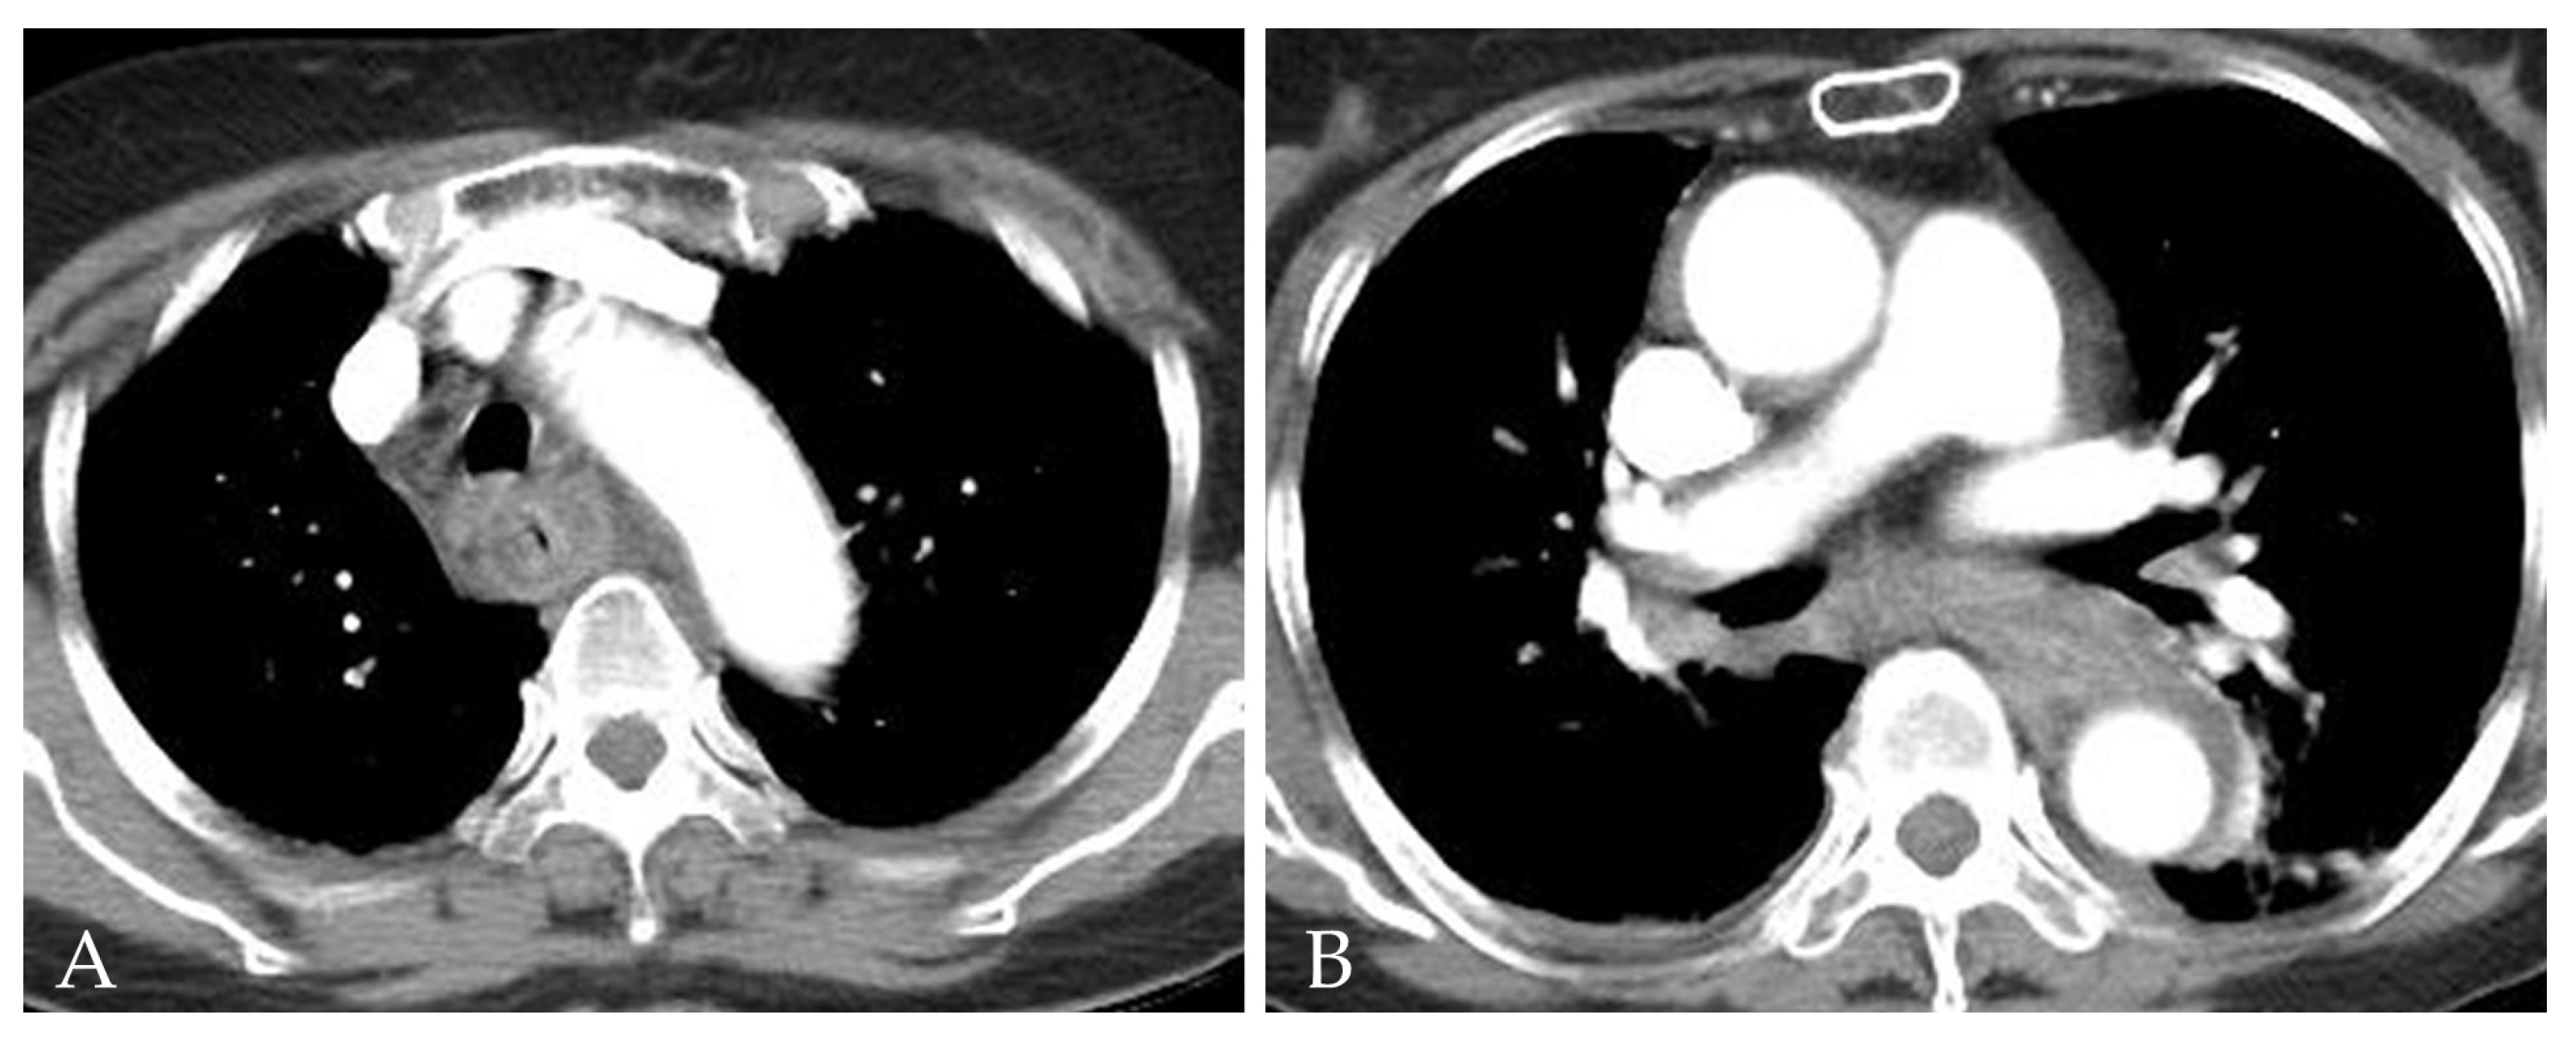

2. Detailed Case Description